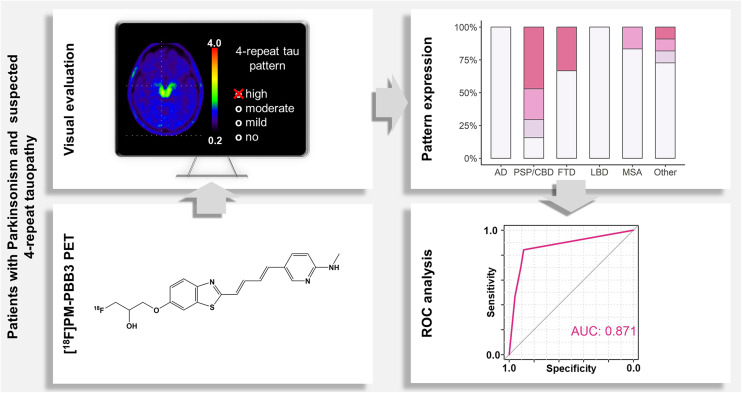

Second-generation tau PET radioligands, which bind to 4-repeat (4R) tau isoforms in progressive supranuclear palsy (PSP) and corticobasal degeneration (CBD), in addition to mixed 3-repeat and 4R tau in Alzheimer disease (AD), may enable tau imaging for differential diagnosis of parkinsonism. The recently proposed ligands 2-(2-([18F]fluoro)pyridin-4-yl)-9H-pyrrolo[2,3-b:4,5c′]dipyridine ([18F]PI-2620) and 1-[18F]fluoro-3-((2-((1E,3E)-4-(6-(methylamino)pyridine-3-yl)buta-1,3-dien-1-yl)benzo[d]thiazol-6-yl)oxy)propan-2-ol ([18F]PM-PBB3, official generic name: florzolotau (18F) or florzolotau) proved to be promising tau biomarkers in patients with suspected 4R tauopathies in several studies, including patients with a clinical diagnosis of PSP (ref. 1,ref. 2) or amyloid-β (Aβ)–negative corticobasal syndrome (CBS) (ref. 3,ref. 4). In patients with CBS, AD ranks as the third most common underlying pathology (∼13%–20%) after CBD (∼24%–55%) and PSP (∼17%–31%) (ref. 5,ref. 6). Therefore, most CBS cases that are Aβ-negative are likely due to either CBD or PSP, which are hard to disentangle clinically (ref. 7). The patterns of cerebral [18F]florzolotau binding in groups of patients with PSP and Aβ-negative CBS significantly differed from the pattern found in AD patients (i.e., closely reflecting neurofibrillary tangle stages in AD) (ref. 8). In turn, the reported patterns in both aforementioned groups are similar: patients with PSP and Aβ-negative CBS exhibit increased subcortical binding in the mid-brain, thalamus, and globus pallidus, and—to varying degrees—cortical binding in the pre- and postcentral gyrus, supplementary motor area, and subcortical white matter (ref. 1,ref. 3,ref. 8). These observations are consistent with the clinicopathologic overlap between PSP and CBD in terms of clinical syndromes and the distribution of 4R tau neuropathology with varying degrees of subcortical or cortical predominance (ref. 7,ref. 9,ref. 10).

Thus, the aim of the present study was to assess the diagnostic performance of [18F]florzolotau PET for identifying 4R tauopathies in a representative clinical cohort of patients with parkinsonism and suspected underlying 4R tauopathy. To improve the accuracy of the reference diagnosis in the absence of autopsy data, we used an interdisciplinary consensus diagnosis incorporating extensive clinical, laboratory, and imaging data. The latter most notably included [18F]FDG PET in virtually all patients, which has been demonstrated to be of high diagnostic value in parkinsonian syndromes and allows accurate distinction not only between AD-CBS and Aβ-negative CBS but also between pathologically verified PSP and CBD (ref. 15–ref. 17). To meet the aforementioned challenges, we first analyzed the accuracy of [18F]florzolotau PET for diagnosing PSP/CBD (joint diagnostic group of clinically likely 4R tauopathies), which was then stratified by the presence or absence of clinical CBS.

PET Analysis

PET acquisition and processing are described in detail in the supplemental materials. All patients underwent a 20-min PET scan 90 min after injection of 356 ± 21 MBq of [18F]florzolotau on a fully digital Vereos PET/CT scanner (Philips Healthcare) (ref. 8). Parametric [18F]florzolotau SUV ratio images scaled to the inferior cerebellar cortex were used for visual analysis. On the basis of prior studies (ref. 3,ref. 8), we defined the 4R-like pattern as locally increased uptake using a standardized color scale (rainbow; SUV ratio range, 0.2–4.0) in the mid-brain, thalamus, globus pallidus, pre- and postcentral gyrus, and supplementary motor area (with possible subcortical or cortical predominance, as described later). The AD-like pattern was defined as locally increased uptake using the same standardized color scale in mesial temporal and neocortical regions (i.e., in temporal, parietal, and frontal cortices and the posterior cingulate gyrus or precuneus) with relative sparing of subcortical structures (except the caudate nucleus) and the primary sensorimotor and visual cortex (ref. 3,ref. 8). Two experienced raters and 1 less experienced rater (all masked to the reference diagnoses and clinical information) rated [18F]florzolotau PET scans on 30 transaxial slices covering the entire brain. The raters classified [18F]florzolotau PET scans according to the presence and expression of AD-like and 4R-like [18F]florzolotau binding patterns using a 4-point scale (0, no; 1, mild; 2, moderate; 3, strong). In presence of a 4R-like pattern, raters subsequently assessed the gradient of the 4R-like pattern by rating the dominance of subcortical (score 0), or cortical (score 2) [18F]florzolotau binding. Comparable binding in subcortical and cortical structures was considered balanced (score 1). After independent evaluation of individual [18F]florzolotau PET scans, the raters reached a consensus score.

The ROC analysis for the consensus score of the 4R-like pattern (PSP/CBD vs. all other patients) revealed AUC of 0.87 (95% CI, 0.80–0.94; range of the 3 raters, 0.78–0.87; highest in experienced raters). The optimal threshold for delineating PSP/CBD from all other disease groups was a score of at least 1 (i.e., at least mild 4R-like pattern), leading to a sensitivity of 84.3% (71.4%–93.0%) and a specificity of 88.4% (74.9%–96.1%). The positive predictive value was 89.6% (77.2%–95.5%), and the negative predictive value was 82.6% (68.8%–93.9%). When stratified in PSP/CBD without and with CBS, ROC analyses yielded comparable AUC (0.89; 95% CI, 0.82–0.96; and 0.82; 95% CI, 0.69–0.95, respectively; Delong test, P = 0.39). When focusing on proper parkinsonian syndromes (i.e., PSP/CBD vs. LBD and MSA), the ROC AUC was also largely unchanged (0.91; 95% CI, 0.85–0.97; P = 0.46).

The present study was conducted in a real-world sample of patients with parkinsonism that reflects the expected indication for tau PET in the clinical routine. It demonstrates that a visually rated 4R-like binding pattern on [18F]florzolotau PET allows the identification of patients with PSP/CBD with high sensitivity and specificity. In addition, a gradient of the 4R-like pattern toward cortical binding was highly associated with the presence of CBS in patients with a 4R-like pattern. Although the AD-like pattern of [18F]florzolotau binding as a marker of (early) AD copathology or possibly primary age-related tauopathy was common in this representative clinical cohort, it did not significantly affect the diagnostic performance of the 4R-like pattern.

Visual evaluation of the 4R-like pattern revealed ROC AUC of 0.87 for the discrimination of PSP/CBD from all other groups, which remained largely unchanged when focusing on proper parkinsonian syndromes (0.91) or excluding all AD patients (0.86). This aligns well with previous findings, which showed AUC between 0.87 and 0.94 for a volume-of-interest–based approach to separate PSP from α-synucleinopathies with [18F]florzolotau PET (ref. 1), and it suggests that the high specificity in this representative sample (88%) is not driven by easy identification of AD-related syndromes. This study validates promising earlier data in a larger clinical cohort that includes not only or predominantly patients with probable or later-stage PSP or PSP-RS and somewhat artificial controls (e.g., AD or healthy controls). Instead, the present sample appropriately covers the entire spectrum of syndromes and diagnoses that would be expected in parkinsonism with possible 4R tauopathies based on clinicopathologic studies (as explained in the introduction). Moreover, current estimates for sensitivity (84%) and specificity (88%) of the 4R-like pattern on [18F]florzolotau PET suggest an advantage in comparison to the second-generation ligand [18F]PI-2620, which allows detection of PSP-RS with high sensitivity (85%, at 77% specificity), whereas non–Richardson-type PSP (65%) and Aβ-negative CBS (65%) were detected with noticeably lower sensitivity (ref. 2,ref. 4). The mean disease duration of patients with PSP enrolled in the aforementioned studies (ref. 1,ref. 2) was longer (4.1 and 3.8 y) than that of the current PSP/CBD group (3.2 y), highlighting the possible value of [18F]florzolotau for earlier diagnosis. Moreover, the simple acquisition protocol and the easy-to-implement workflow for visual image analysis provide practical advantages compared with [18F]PI-2620 (60-min acquisition and kinetic modeling) (ref. 2). Cases of FTD and MSA with 4R-like pattern expression (1 patient each) are in line with the previous literature and may be related to the occurrence of 4R tau pathology in nonfluent variant primary progressive aphasia and behavioral variant FTD (ref. 26,ref. 27) or to misclassification because of possible off-target binding of [18F]florzolotau in MSA (ref. 28).

CONCLUSION

Based on a real-world population of patients with parkinsonism and possible 4R tauopathy, we demonstrate that simple visual evaluation of a priori–defined binding patterns on [18F]florzolotau PET allows highly accurate identification of patients with the clinical consensus diagnosis of PSP/CBD (clinically likely 4R tauopathies), including a stratification in subgroups without and with CBS. Thus, [18F]florzolotau PET is a promising biomarker for the differential diagnosis of neurodegenerative parkinsonian syndromes.